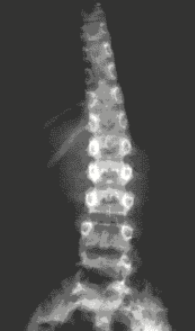

- Lumbar X ray shows scoliosis w/ right concavity

- Bone scintigraphy: pathological uptake in L1